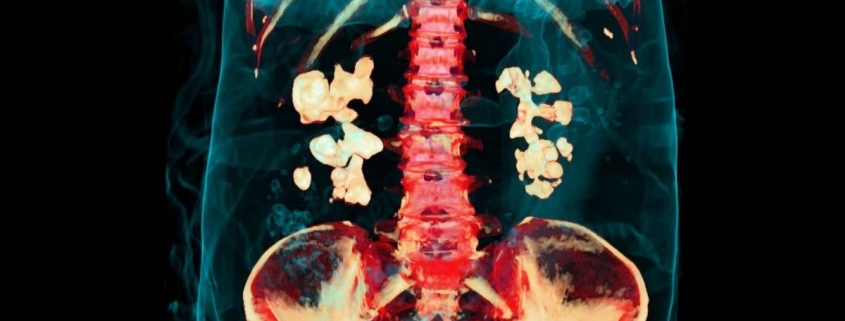

In a mind-blowing discovery that’s sending shockwaves through the medical community, researchers have uncovered a shocking secret hiding inside the most common type of kidney stones. These painful mineral formations aren’t just lifeless crystals – they’re actually teeming with live bacteria and complex biofilms!

A groundbreaking study from UCLA has revealed that calcium oxalate kidney stones – which account for a whopping 80% of all kidney stone cases – contain living bacteria and biofilms embedded within their crystalline structure. That’s right, these stones aren’t just sitting there like inert rocks; they’re actually biological hotspots!

Using cutting-edge electron and fluorescence microscopy techniques, the research team discovered that bacteria and their biofilm components are woven throughout the stone’s structure, alternating with crystal layers like some kind of microscopic lasagna. These aren’t just surface contaminants – they’re embedded deep within the stone itself!

Here’s where it gets really interesting: the researchers suggest we should start thinking of kidney stones as “organic-inorganic biocomposites” rather than just mineral deposits. In other words, they’re part living, part mineral – a hybrid material that’s been hiding in plain sight!